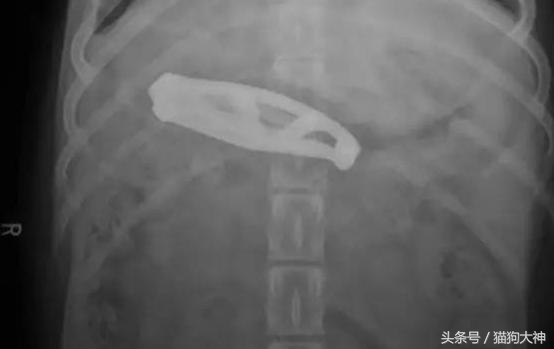

这只狗狗趁主人不注意,吞下了一把折叠刀,发现不对的主人赶紧送它去了医院。

所幸主人把不用的小刀折叠好了,狗狗并没有什么大碍。

但狗狗傻起来简直让人目瞪口呆,这只狗狗竟然吞下了一把这么长的刀!不是所有狗狗都有能化险为夷的好运气,所以就需要主人留心帮它们排除生活在可能存在的危险。